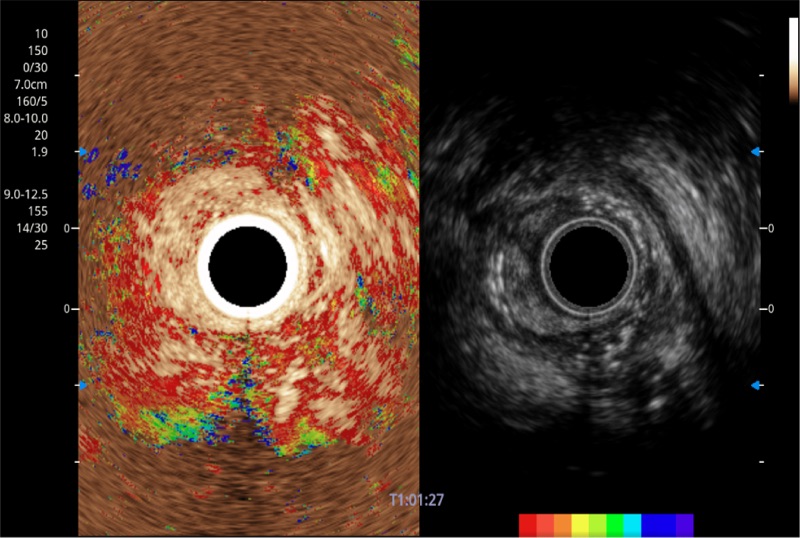

可人为将灰阶图像转变成彩色的显示方式,增强人眼对于不同回声强度的敏感度,主观上增加了图像分辨率

具有四种造影成像效果

肝左叶和肝静脉的横截面